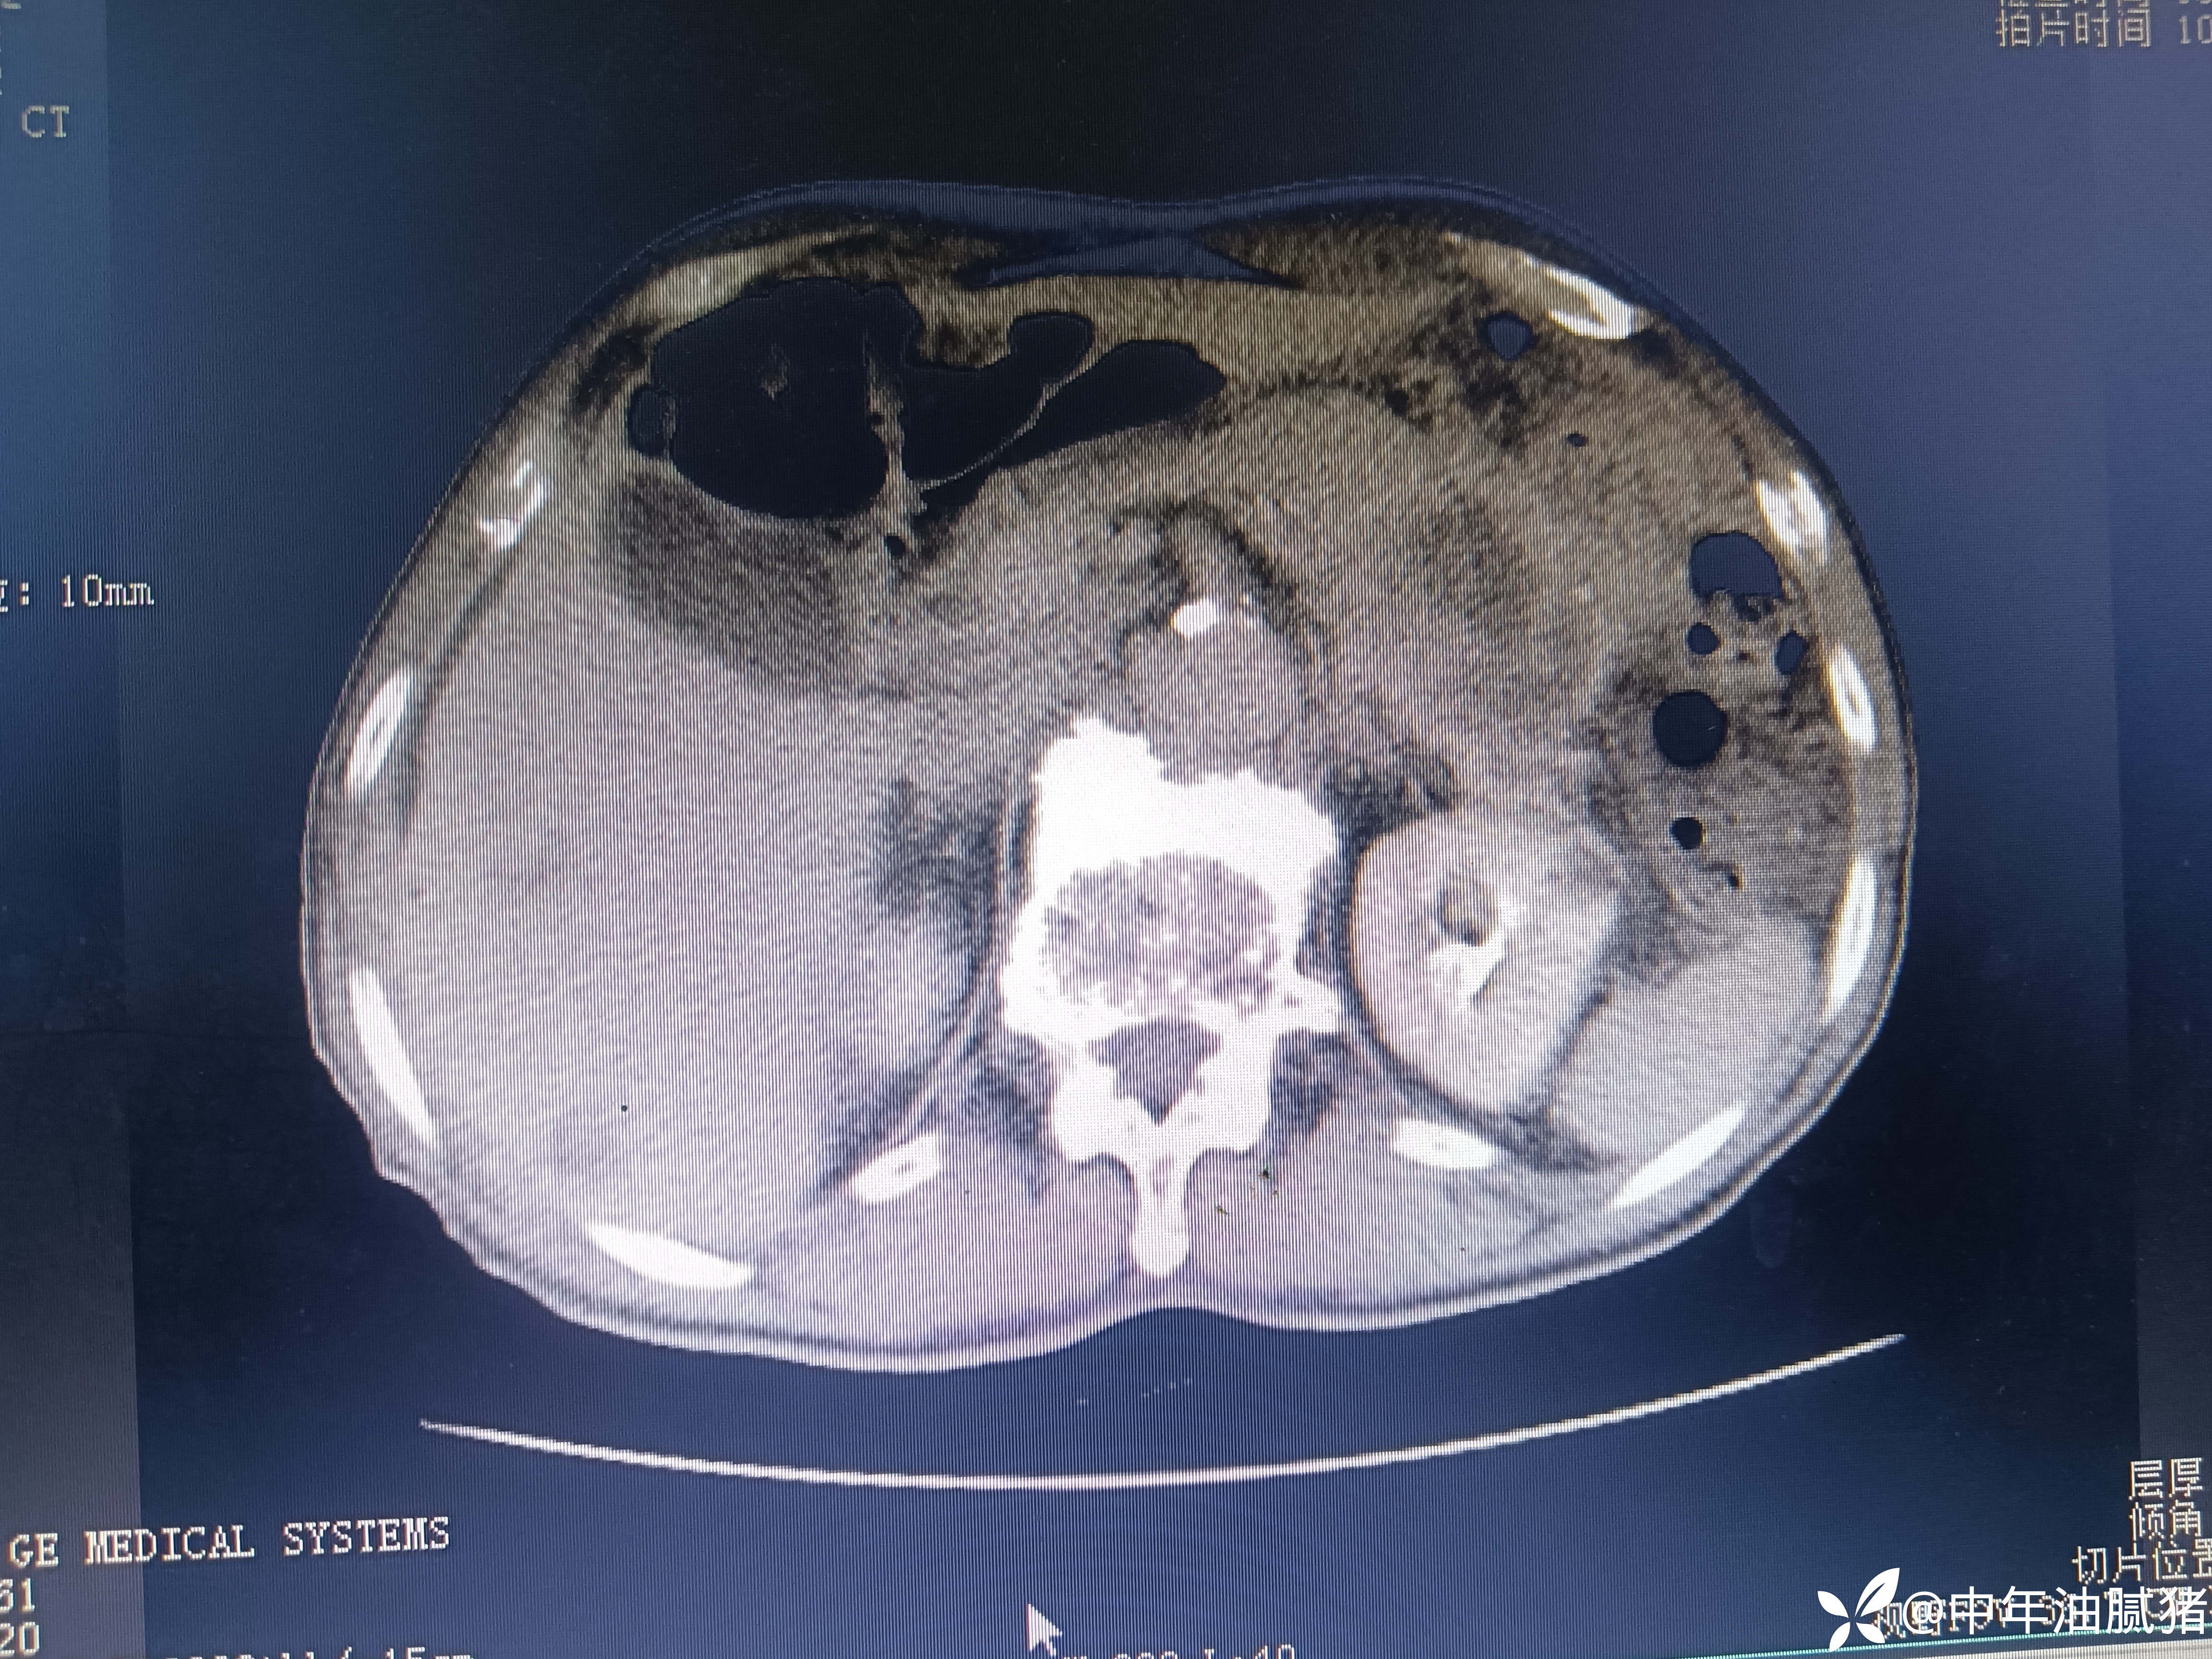

肺ct看到肝内病灶,行增强检查

建议增强ct.报告如下

考虑肝囊肿?让他走?

看后,我隐隐约约觉的不是肝囊肿那么简单?元芳,你怎么看?狄阁老,我也是这么认为!摇人,掏起手机:喂,w主任,请帮我看看这个ct。5分钟后报告修改如下